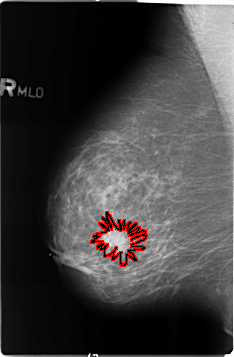

B_3488_1.RIGHT_MLO

RIGHT_MLO LINES 4640 PIXELS_PER_LINE 3040 BITS_PER_PIXEL 12 RESOLUTION 50 OVERLAY

FILE: B_3488_1.RIGHT_MLO.OVERLAY

TOTAL_ABNORMALITIES 1

ABNORMALITY 1

LESION_TYPE MASS SHAPE IRREGULAR-ARCHITECTURAL_DISTORTION MARGINS SPICULATED

ASSESSMENT 5

SUBTLETY 5

PATHOLOGY BENIGN

TOTAL_OUTLINES 1

BOUNDARY